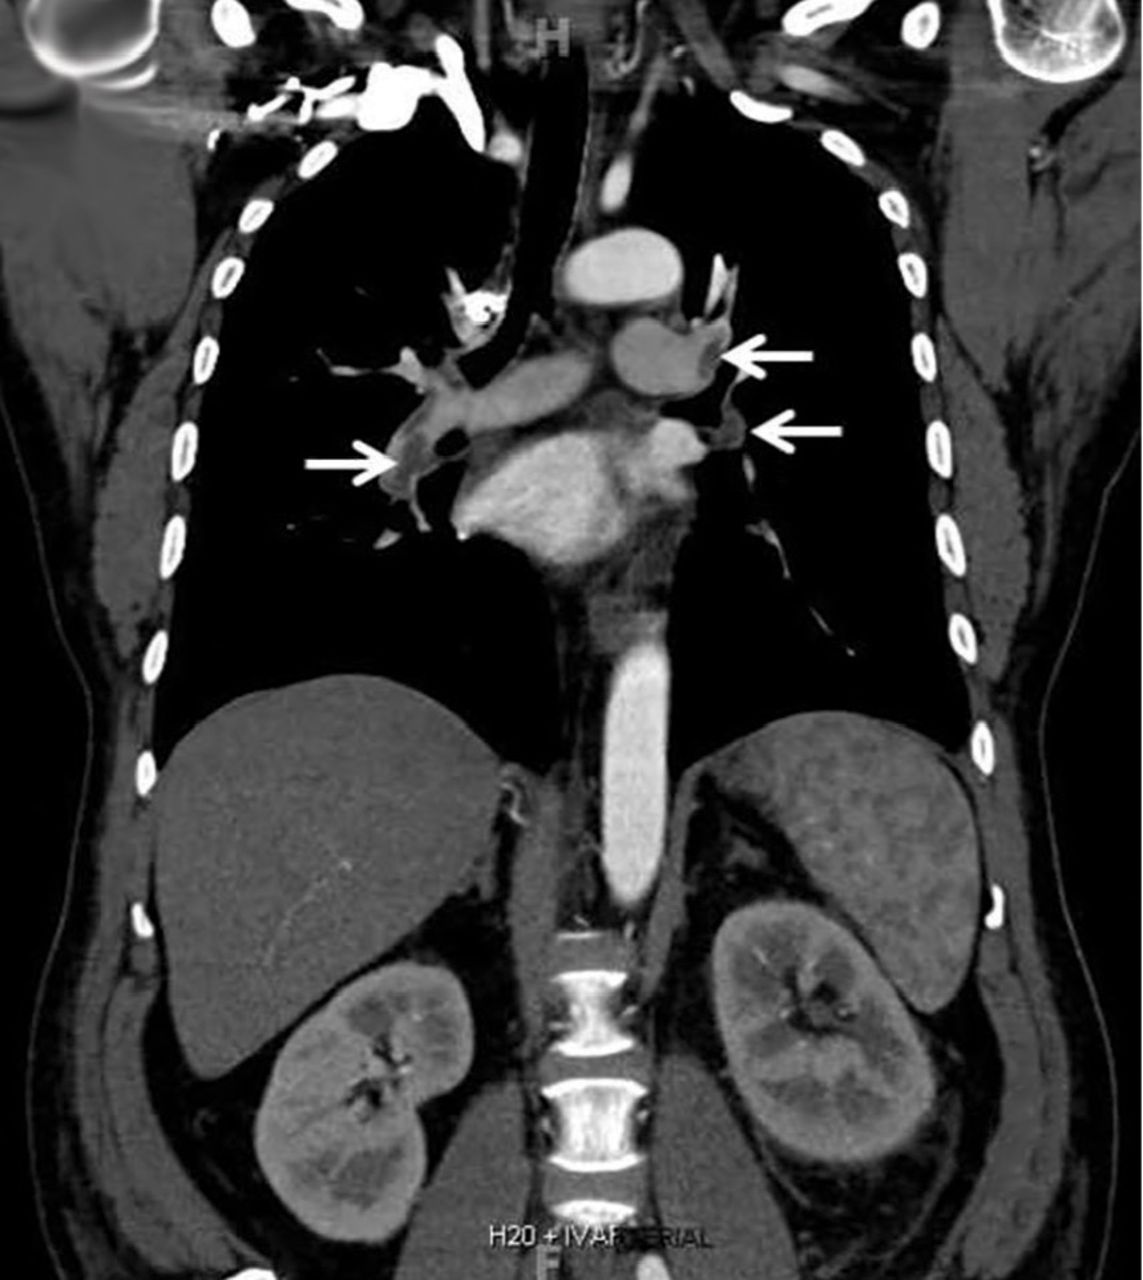

Computed tomography of the chest and abdomen with intravenous contrast demonstrated a nearly occlusive thrombus in the left renal vein (Figure 1) extending to the inferior vena cava with bilateral, nearly occlusive pulmonary emboli (Figure 2).

Coronal reformatted contrast-enhanced computed tomography of the chest showed bilateral low-attenuation filling defects in the pulmonary arteries (arrows).